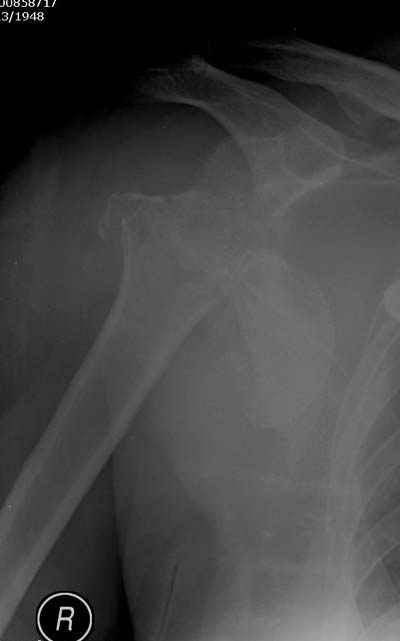

Женя, а как ты водишь спицы, в смысле, как делаешь входное отверстие, и как в него проводишь V-спицу? А то о дна из спиц, та, у которой не дошла до головки одна палочка буквы V, как-то выглядит на рентгенограмме, как будто или через очень большое отверстие введена, или каждая половинка через отдельные отверстия.

В чем ты видишь причину вторичного смещения?

Мне кажется, проблема в том, что не все концы спиц зашли в головку, и зашедшие - недостаточно далеко прошли.

С комментариями абсолютно согласен.

Спицы провожу по передней и задней поверхностям плечевой кости через 4,5 мм отверстия на разных уровнях.

Идеей презентации случая была демонстрация важности постоп Рг - хотя казалось бы все было сделано под флюороскопическим контролем и интраоперационно подозрений на нестабильность не возникло, а такая вот

неожиданность...

V-спица проводится через 4,5 мм отверстие. Видимо, из-за разной длины вторая половина спицы *пролетела* мимо отверстия, что и привело к вторичному смещению костных фрагментов.